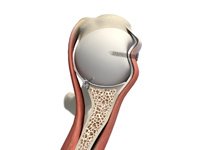

Shoulder Joint Replacement

The shoulder is a highly movable body joint that allows various movements of the arm. It is a ball and socket joint, where the head of the humerus (upper arm bone) articulates with the socket of the scapula (shoulder blade) called the glenoid. The two articulating surfaces of the bones are covered with cartilage, which prevents friction between the moving bones.